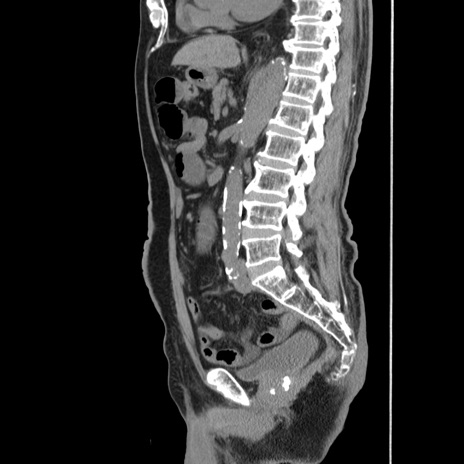

症例24(矢状断像)

冠状断像